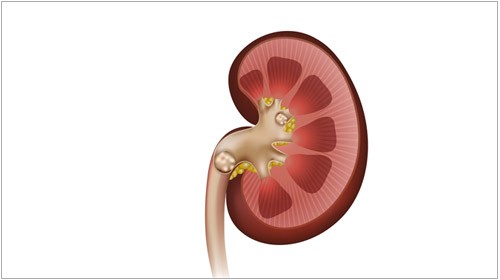

요로결석은 비뇨기관에서 소변의 성분들이 결정으로 변하여 돌이 형성되는 질병입니다.

요로결석은 소변이 만들어져 배출되는 길인 요로에 결석이 생기는 질환입니다. 결석은 주로 칼슘, 수산염, 인산염 등의 무기질이 소변에 녹지 못하고 결정으로 뭉쳐져 생성됩니다.

요로결석은 신장, 요관, 방광, 요도 등 어디에서나 생길 수 있지만, 가장 흔하게는 요관에서 생깁니다. 요관은 신장에서 방광으로 소변을 운반하는 관으로, 지름이 약 5mm 정도입니다. 결석이 요관에 생기면 통증, 구역질, 구토, 혈뇨 등의 증상이 나타날 수 있습니다.